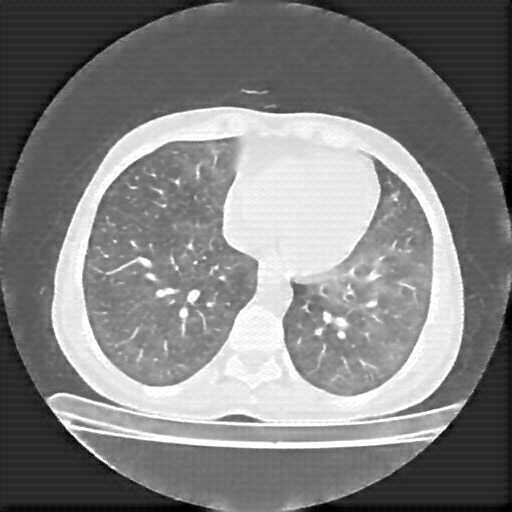

Original NATIVE CT scan (input)

No window - Raw intensity values

Lung window (WL -600, WW 1500 β†’ Low βˆ’1350, High +150)

Mediastinum window (WL 40, WW 400 β†’ Low βˆ’160, High +240)